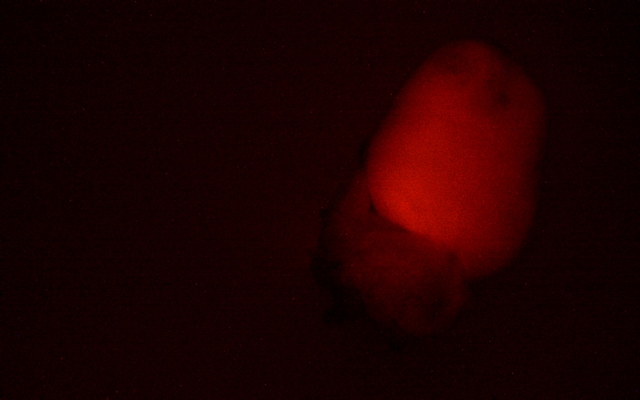

MZX81顯微鏡以其出色的明場和熒光成像能力,為科研人員提供了清晰銳利的觀察體驗。在明場模式下,心臟組織的細微結構一覽無余,細胞輪廓分明,為后續的深入分析奠定了堅實基礎。而切換到熒光模式時,MZX81又能夠精準捕捉熒光標記信號

小鼠心臟

更值得一提的是,MZX81體視熒光顯微鏡擁有1:7的大變倍比,這意味著科研人員能夠在不同放大倍數間自由切換,既能把握整體的心臟構造,又能深入到細胞甚至分子層面進行探索。這一特點在模式生物研究中尤為重要,它滿足了科研人員對多層次、多角度觀察的需求,為揭示生物體的奧秘提供了有力工具。

熒光標記小鼠心臟